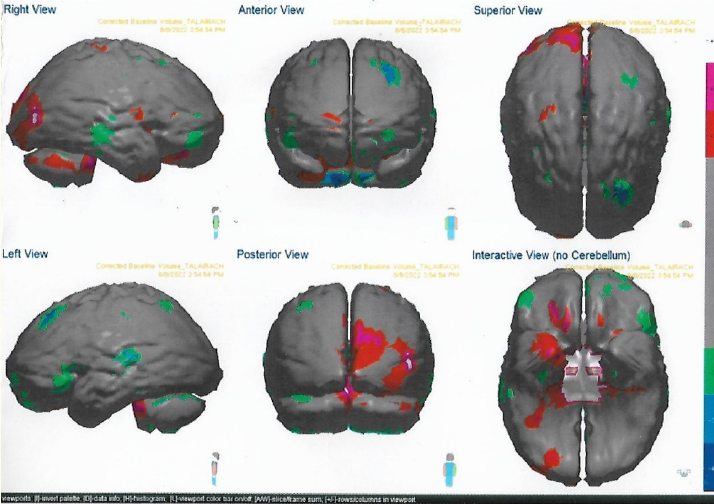

Massive Brain Hemorrhage in a Patient with Brain, Lung and Colon Metastases: A Rare Case Report

Seshadri Thirumala, Robert Scranton, David Jenkins, Ganesh Tallam, Timothy Miller and Isaac Tafur. 5(11): 81-86.